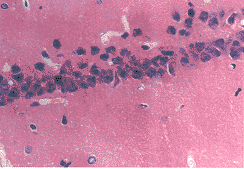

图1 正常对照组海马 CA1区锥体细胞排列整齐而致密 HE×132

图2 假手术7天组海马CA1区锥体细胞数目和形态同正常组 HE×132

图3 VD模型7天组海马CA区锥体细胞排列紊乱,脱失严重,胞核浓染 HE×132

图4 中药防治7天组海马CA1神经元排列较规则,细胞较规则,细胞轻度脱失,部分胞染变深 HE×132